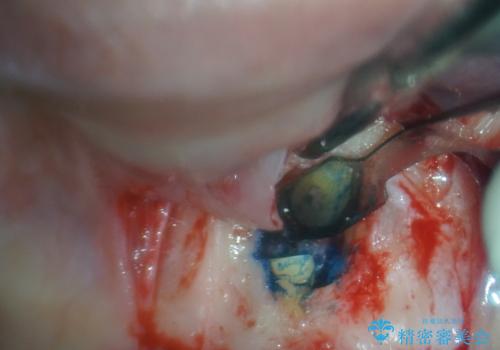

治療の選択肢としては、①セラミッククラウンを壊して再度根管治療を行い、その後セラミッククラウンを製作する、②当該歯の歯根端切除術を行う、のいずれかとなります。

歯根端切除術では、術後に歯肉ラインが偏位し、セラミッククラウンと歯の境目が目立つことがありますが、患者様と相談の上、②歯根端切除術にて治療を行うこととしました。